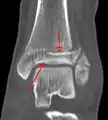

A triplane fracture of the ankle as seen on plain X-ray

A triplane fracture of the ankle as seen on CT

- Triplane fractures are a special type of fracture that involves the immature skeleton. It has a coronal plane in the metaphysis, an axial plane in the physis, and a sagittal plane in the epiphysis.[14]